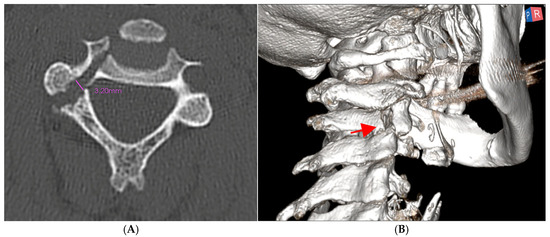

2.1. Preoperative Planning